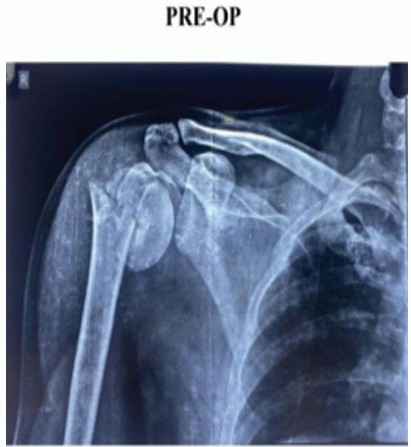

Informed consent was obtained from all participants. Demographic details and relevant medical history were collected using a structured proforma. Clinical examination and surgical intervention were carried out using standard procedures at the SBMCH. [Fig. 1] [Fig. 2] [Fig. 3] Postoperative evaluation for implant loosening was done through serial radiographs, specifically assessing for radiolucency at the bone-cement interface. Functional outcomes were assessed 26 using the CONSTANT-Murley score and UCLA shoulder score. All data were entered in Microsoft Word and analyzed using SPSS software version 24. [Fig. 4].

Figure 1: Pre-operation X-ray.